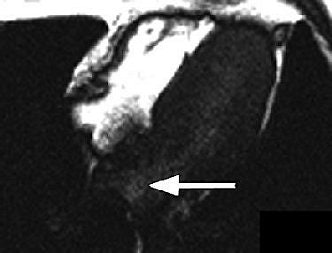

| Thirty-two-year-old man with PFO grade 3 on TEE and grade 3 on MRI. Above and below, images show enhancement of entire left atrium due to right-to-left-shunting (arrows) before enhancement of pulmonary vein. Mohrs OK, Petersen SE, Erkapic D, Rubel C, Schräder R, Nowak B, Fach WA, Kauczor HU, Voigtlaender T, "Diagnosis of Patent Foramen Ovale Using Contrast-Enhanced Dynamic MRI: A Pilot Study" (AJR 2005; 184:234-240). |

The results showed that PFO was visually identified in all 15 patients, and excluded in the control group on MRI. For the patients with PFO, "an early contrast enhancement due to intracardiac right-to-left shunting was present in the left atrium before the contrast agent reached the pulmonary veins," the authors wrote. There was a 20% prevalence of atrial septal aneurysm in the PFO population, and MRI correctly identified these cases.